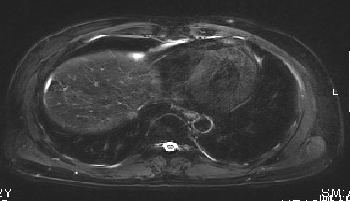

MRI:

入院诊断:

1.原发性肝癌(右,多发)伴门静脉右支癌(BCLC C期,中国2017版规范Ⅲa期)

2.乙型肝炎肝硬化

3.门静脉高压症